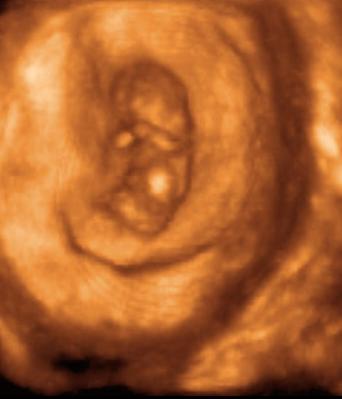

Majd nézzétek meg milyen kis cuki a 8ik héten a baba :lol: Kép 8 hetes baba

Gurgula! Nagyon édes a baba. Hihetetlen, hogy szinte már mindene megvan. Kivettem egy könyvet a terhességrööl a könyvtárból, abban megvan hétrööl-hétre, hogy mekkora a baba és életnagyságú képekkel. Nagyon aranyosak.

Az UH egyébként a tarkóredőmérés lesz, nálunk tehát 13+1-en. Majd megpróbálom bescannelni a kis csodagyerek fotóját 8) :lol: